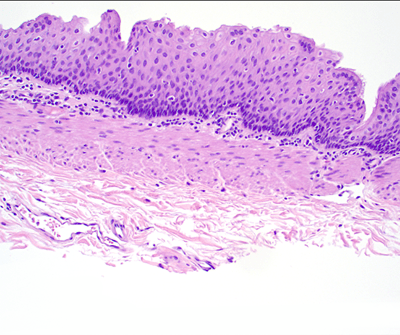

Figure 2. Closer view of the cyst shows ciliated pseudostratified columnar epithelium with muscularis mucosa and submucosal mucinous glands (10x). Hyaline cartilage is notably absent. The inset at the top right provides a closer view of the cilia (40x).